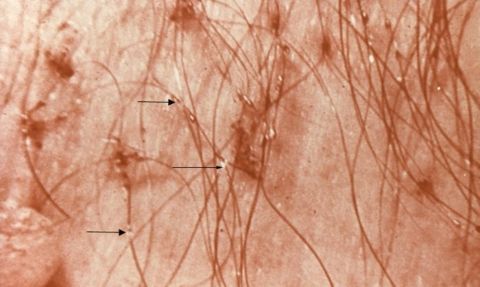

Uyuz: Uyuz hastalığı